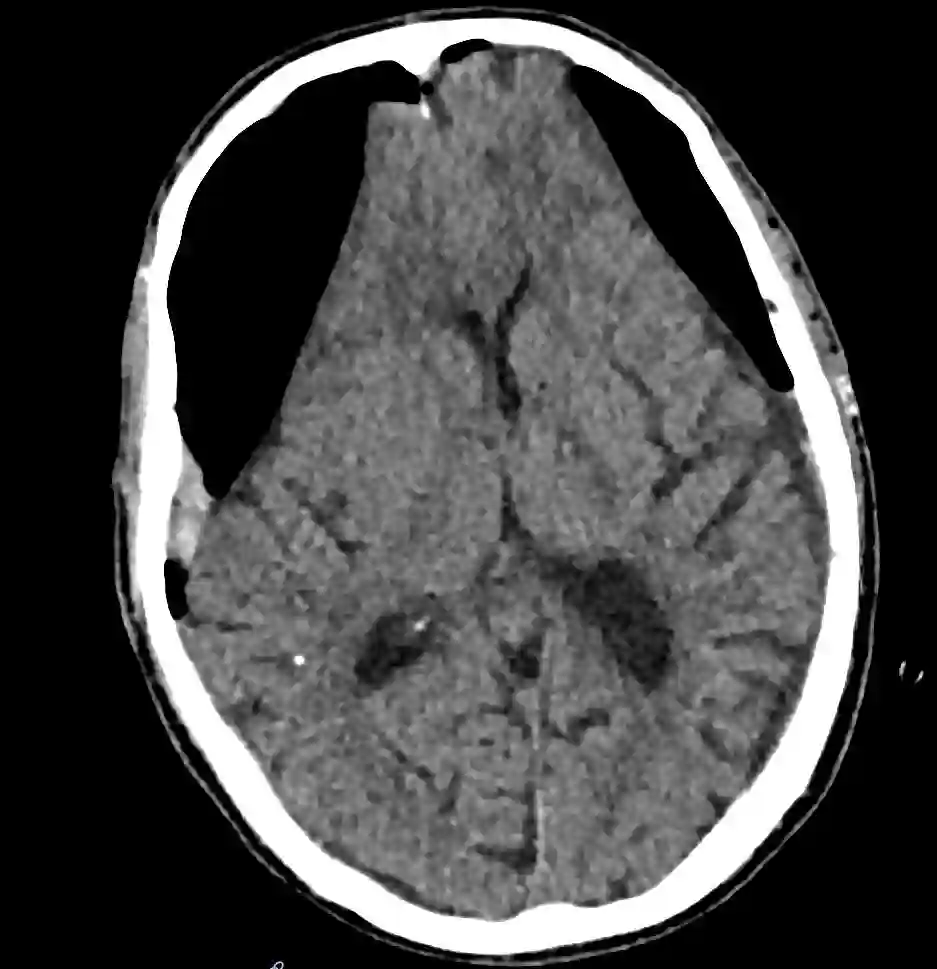

Die intrakraniellen Lufteinschlüsse lassen sich optimal in einer CT-Bildgebung als auch in einer MRT Bildgebung darstellen. Ein ausgeprägtes Pneumocephalus mit Kompression des Frontallappens kann sich in der CT-Bildgebung als sogenanntes Mount Fuji Zeichen darstellen.

CT